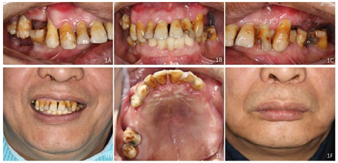

口外检查:颌面部大致对称,面下1/3前突,双侧颞下颌关节未见异常(图1)。

面照;F:正面照

面照;F:正面照口内检查:15、16、24、25、26、27缺失,缺牙区牙槽嵴低、窄;14、12、11、21、22Ⅲ度松动、17Ⅱ度松动、18Ⅰ度松动,牙龈退缩,部分牙根暴露,前牙呈扇形分开,高笑线。31、32、41、42缺失,已行31、32、33、41、43烤瓷固定桥义齿修复(5单位);36缺失,37近中倾斜,近中邻面及远中邻

面可见黑色龋坏组织,质软,探诊、冷诊不适,叩诊(一);47缺失,缺牙区牙槽嵴低平,46牙龈退缩,根分叉暴露,

面可见白色充填物,完整。未见龈上结石,全口牙牙龈退缩,部分牙根外露。前牙重度深覆

重度深覆盖,双侧后牙无稳定咬合关系(图1)。